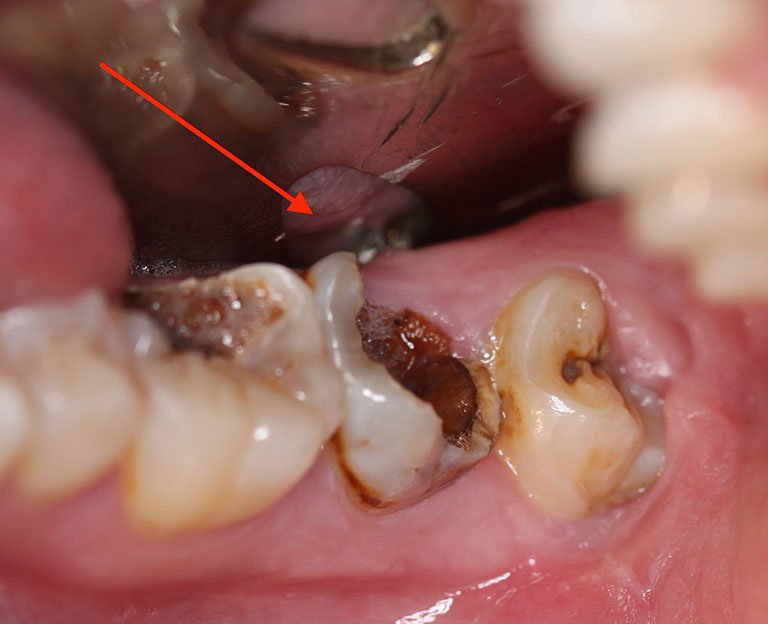

- Sâu răng: Đây là nguyên nhân hàng đầu dẫn đến nhổ răng. Nếu sâu răng không được điều trị kịp thời, nó có thể lan rộng, làm hỏng tủy răng và gây viêm nhiễm, dẫn đến việc phải nhổ.

Sâu răng cũng là nguyên nhân khiến bạn phải nhổ răng